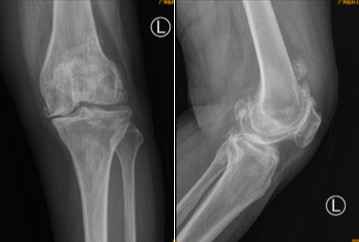

术前X光检查显示何阿姨左膝关节软骨完全磨损,髌上囊及股骨后髁大量骨赘增生,何阿姨尽管行动不便、疼痛难忍,却对手术顾虑较大。“如果不进行手术根治,日后不但难以行走,更会因为长期不运动,使得心肺功能下降,原有的高血压、糖尿病等基础疾病也难以控制。”张弛分析了手术的必要性和有效性,最终患者和家属一致决定进行手术,但手术的难题却也如同“拦路虎”一样出现。

术前X光片提示患者左膝关节软骨完全磨损,髌上囊及股骨后髁大量骨赘增生。